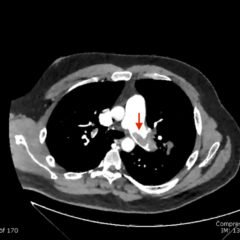

Significant findings:

A CT scan of his abdomen/pelvis shows acute sigmoid colonic diverticulitis with adjacent extraluminal collection containing gas (axial view, white arrow) consistent with perforation, along with abutment of the urinary bladder with intraluminal bladder gas (sagittal and coronal views, white arrowheads) suggesting colovesicalfistula.

A colovesicalfistula (CVF) is an abnormal connection between the colon and urinary bladder.1 Although uncommon, CVFs can cause significant morbidity and may lead to death, usually secondary to urosepsis.1,2 These fistulas are most commonly complications of diverticular disease, inflammatory bowel disease, or cancer.3 Up to 20% of patients with diverticular disease and up to 1% of patients with Crohn’s disease are found to have a fistula.4,5 Pneumaturia or fecaluria can be seen in up to 90% of patients.6 Other presenting signs/symptoms include dysuria, suprapubic pain, frequency, urgency, and rarely, gross hematuria.3 The diagnosis of a colovesicalfistula is confirmed by abdominopelvic CT scan with oral or rectal contrast demonstrating air or contrast material in the bladder with adjacent colon and bladder wall thickening. This type of diagnostic imaging has been shown to have a sensitivity of 90 to 100 percent.3